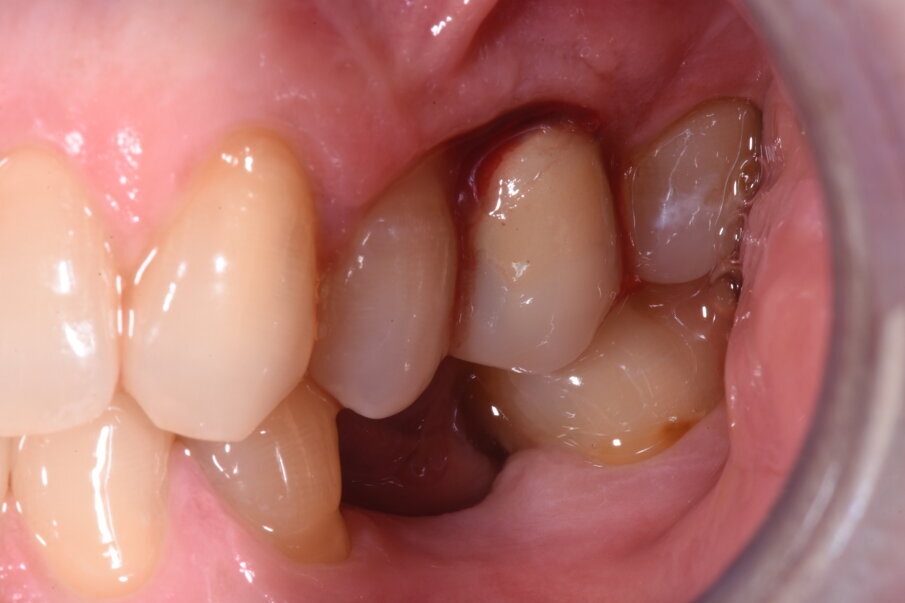

La paziente si presenta all’attenzione dello studio riferendo fastidi nella zona superiore sx, e all’anamnesi risultano trascorsi 3 anni dall’ultimo appuntamento di igiene presso altro centro. L’esame visivo e fotografico (Fig. 1) evidenziano un’alterazione dello stato dei tessuti perimplantari con sanguinamento spontaneo e lassità del tessuto molle, pertanto segue acquisizione di rx endorale da parte dell’odontoiatra (Fig. 2) da cui risulta un’importante riassorbimento osseo a carico dell’impianto. Segue un sondaggio perimplantare profondo (Fig 3), eseguito previa anestesia topica con Lidocaina 15%, per definire estensione e conformazione del difetto associandolo alla valutazione radiografica per la conta delle spire esposte.

Fig. 1